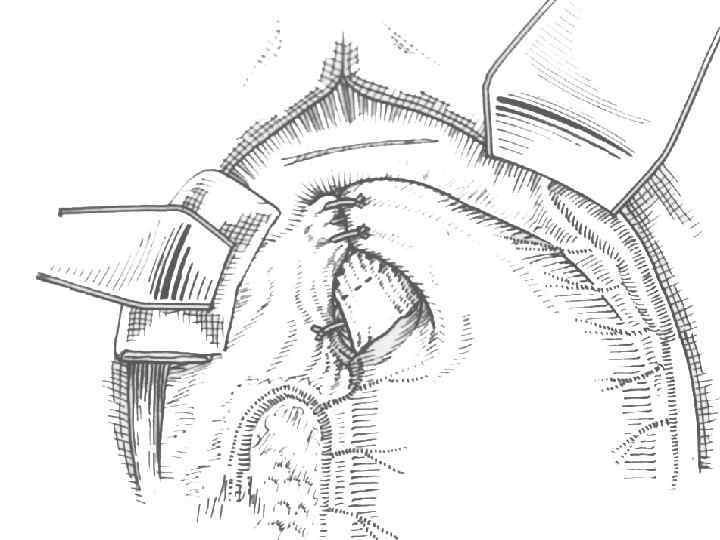

Ромбовидная пилоропластика. В виде ромба рассечена передняя порция пилорического жома и гастроанастомоз

Наложение первого ряда швов по Пирогову-Матешуку